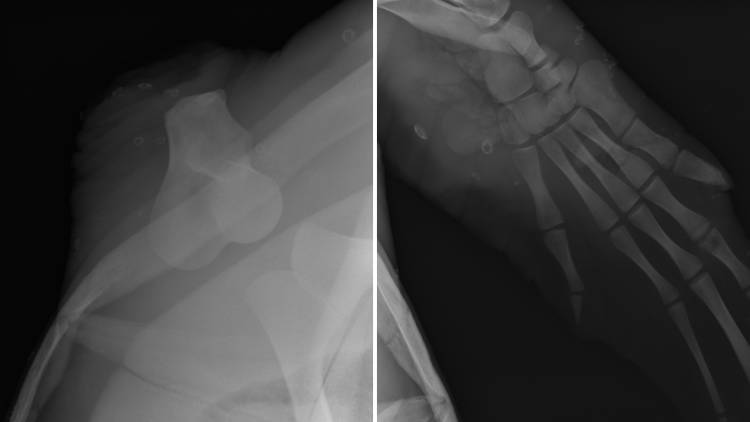

An X-ray of Geri's stump, alongside her injured, but remaining, flipper.